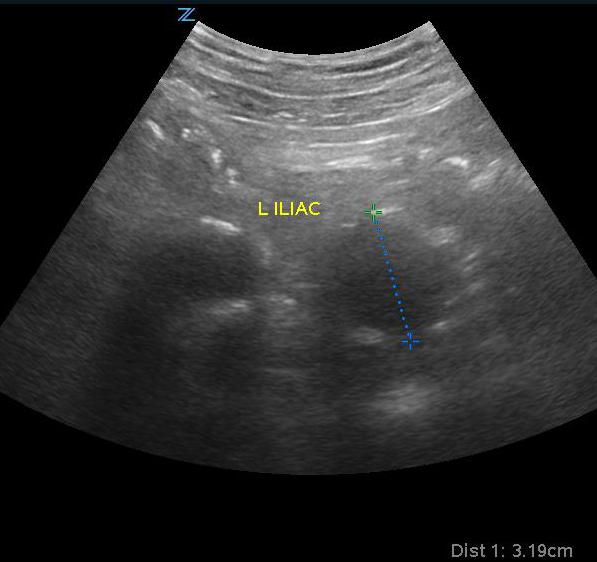

- Iliac artery aneurysm is outside of the purview of emergency medicine and bedside ultrasound but if noted to be larger than >1.85 cm for a man and >1.5 cm for a woman, appropriate follow-up should be organized as significant risk of rupture and death are associated with isolated iliac artery aneurysm.16

- Figure 8. Iliac artery aneurysm